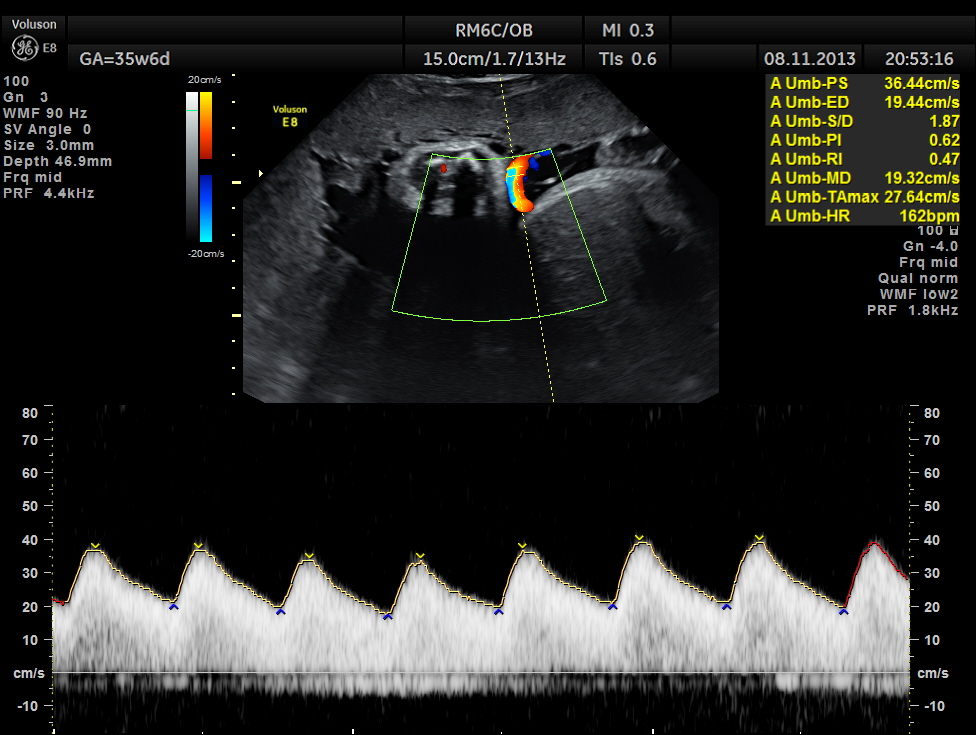

The umbilical artery doppler appeared to be normal. MCA was technically difficult to access.

the umbilical artery doppler appears normal.